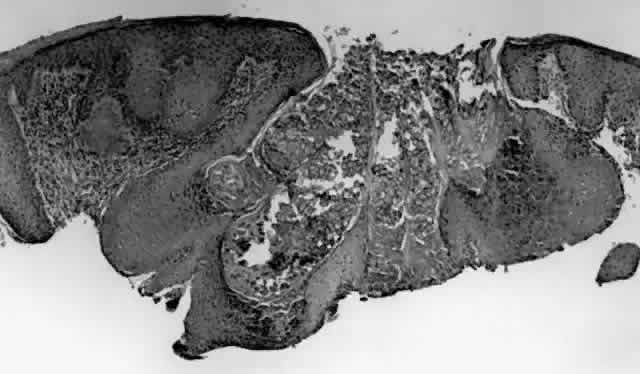

Molluscum contagiosum is a papule with lobular downgrowth of epithelium into the dermis and a central “crater” on the surface (Fig. 11). The epithelium and infected cells demonstrate hyperplasia. Basal cells divide more rapidly (6.1 day turnover decreasing to 3.4 days) and infected cells show more rapid migration through the epithelium as well as cessation of host DNA transcription.121,122 Each lobule demonstrates a progression from base to top. The malpighian cells contain eosinophilic elementary bodies (Fig. 12). These coalesce to form a hyaline molluscum body (HendersonPaterson body).123 The cytoplasmic molluscum bodies increase in size until they distort and displace the nucleus, sometimes becoming larger than the original host cell (Fig. 13). At the top of the lobule in the granular cell layer, the Henderson-Paterson inclusion body changes from eosinophilic to basophilic. When the overlying stratum corneum loses its integrity, the crater is formed (see Fig. 10). Microdissection revealed124 and scanning electron microscopy confirmed125 the presence of a sac surrounding the viral inclusion body within each cell, which has been speculated to provide an immunologically sheltered site for viral reproduction.

Fig. 11. Molluscum contagiosum, histology. Low-power view of lobular epithelial downgrowth and central umbilicated crater. (Original magnification × 50)

Fig. 12. Molluscum contagiosum, histology. Evolution of molluscum bodies from base (left) to center of lobule (right). (Original magnification × 200)

Fig. 13. Molluscum contagiosum, histology. High-power view of transition zone. Molluscum bodies are apparent (right). Note the dark, displaced nuclei. (Original magnification × 400)